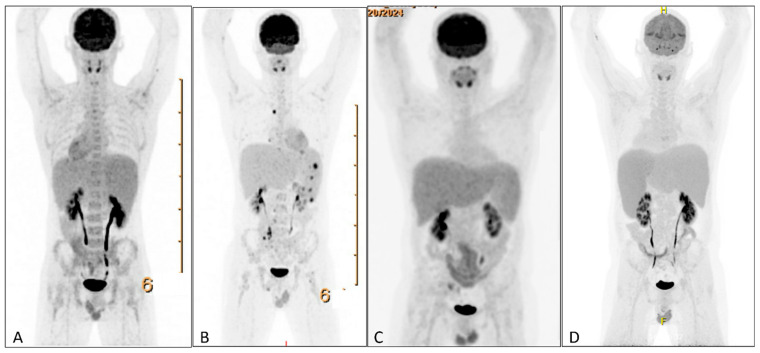

Background and Significances: In patients with Epstein-Barr virus-driven hemophagocytic lymphohistiocytosis (EBV-HLH), identifying the underlying cause poses a significant diagnostic challenge. HLH may precede overt disease, and early directed treatment for HLH can obscure histopathological findings. A liquid biopsy enables the detection of tumor-derived DNA from various sources, including cell-free DNA, circulating tumor cells, extracellular vesicles, and tumor-educated platelets, and might aid in this setting. Case Presentation: This case presents a young patient with EBV-HLH, in which genomic analysis of tumor-derived DNA from circulating tumor cells led to the diagnosis of an EBV-positive NK/T-cell lymphoma-where conventional tissue biopsies had failed. Conclusions: This report underscores the potential of the liquid biopsy as a valuable diagnostic tool in complex cases of EBV-HLH.